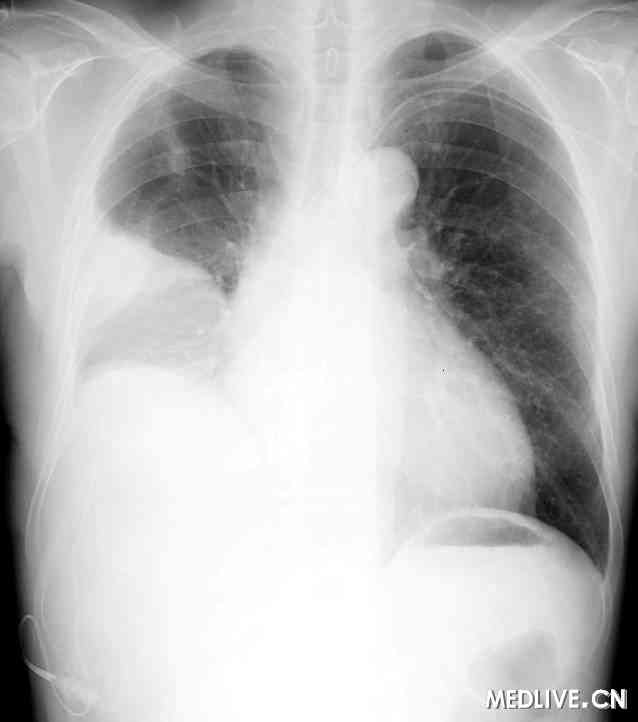

在此情况下,我们决定在建立心包窗后2个月时采用丹佛分流管行胸膜腹膜分流(见图2)。从第5肋间向右侧胸膜腔插入1根有孔的细胸膜导管(16 Fr),并通过1个皮下通道将其连接到主泵上,后者有2个单向阀并被固定在右侧肋部边缘皮下。穿过右上腹直肌向腹腔插入1根腹膜导管(见图3)。结果,该患者的乳糜胸明显好转,相应症状消失(见图4)。患者在17个月后死亡,在死亡前不再需要对乳糜胸采取进一步治疗,胸膜腹膜分流也未出现任何问题。

图2  丹佛胸膜腹膜分流管